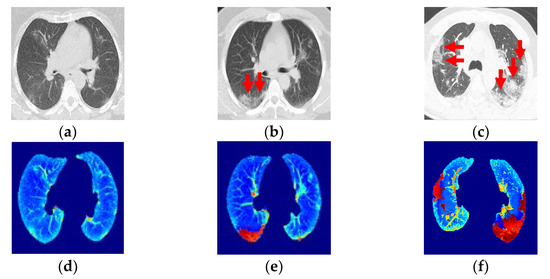

2.2. Ground-Glass Opacity and Pulmonary Infiltrates Highlighted by Saliency Fusion

3.2. Quantitative and Qualitative Evaluation of PP and GGO–PI Identification